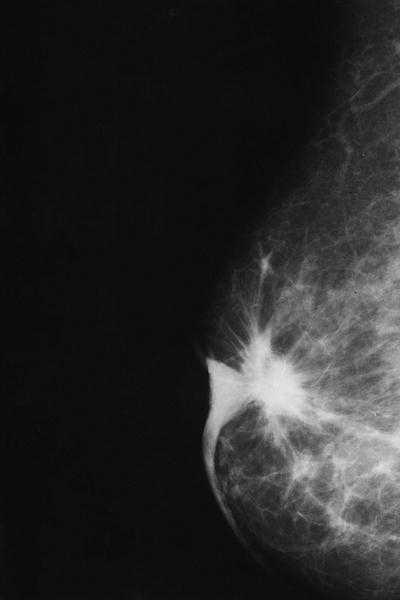

La radiografía de tórax revelaba una cardiomegalia y campos pulmonares claros. Según la mamografía bilateral, en localización retroalveolar de la mama izquierda había una imagen nodular de alta densidad y bordes espiculados de unos 2 cm de diámetro, que se asociaba a retracción del pezón y engrosamiento cutáneo (fig. 1). La lesión era altamente sospechosa de malignidad.

La mamografía de la mama derecha resultó normal.